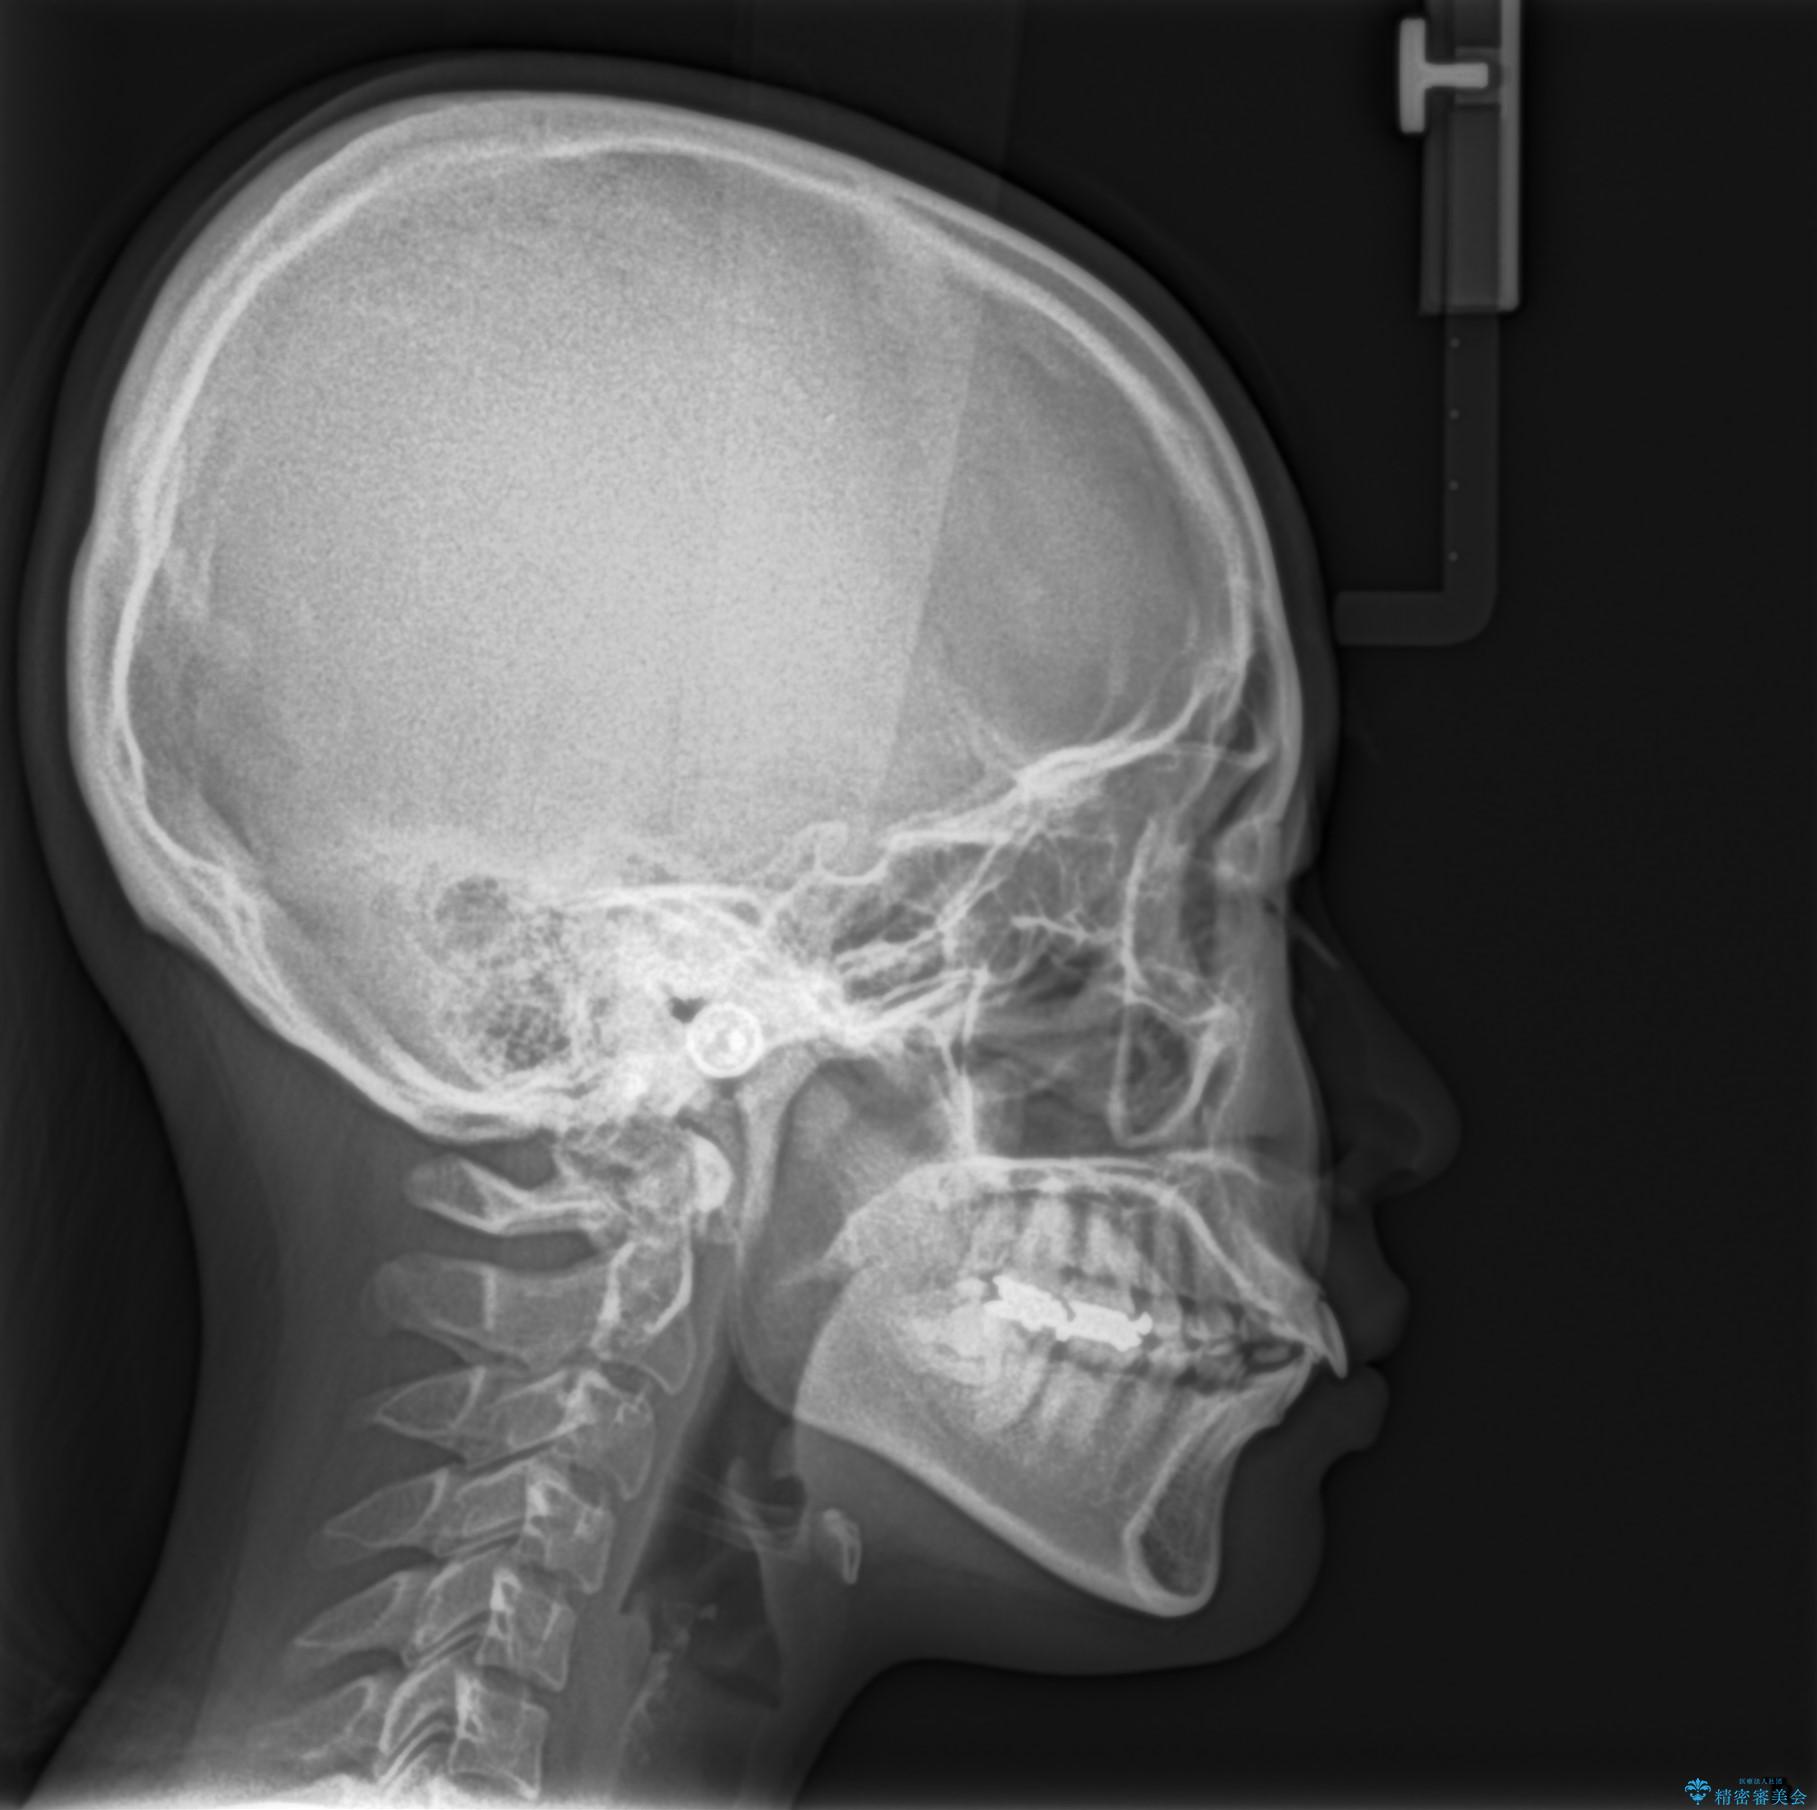

- 口元が出ていることを主訴に来院されました。

上下左右小臼歯を抜歯して審美装置で治療を行いました。

口元もスッキリと変化し、大変満足していただきました。

抜歯したスペースをきちんと下げることができるように、矯正用のアンカースクリューを用いて治療をしております。